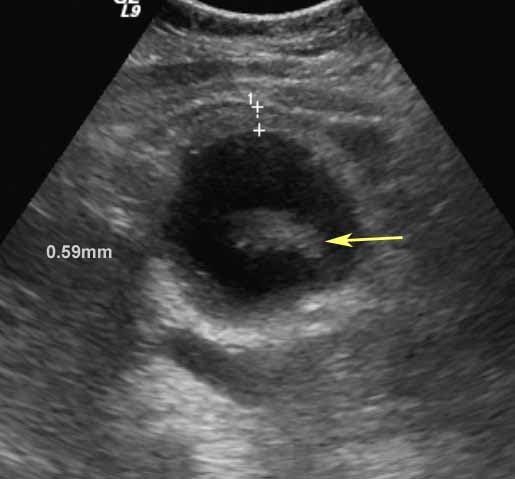

Is Gallbladder Wall Thickening Dangerous. Thickening of the gallbladder wall is a relatively frequent finding at diagnostic imaging studies. Thickening of the gallbladder wall can be seen on the ultrasound as well and usually is a result of inflammation.